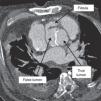

A 68-year-old man with a history of systemic hypertension and chronic renal failure was admitted to our emergency department with chest pain and dyspnea. He had undergone tube graft replacement of the ascending aorta due to an acute type A aortic dissection 10 years previously. On admission he was hypertensive and tachycardic with a continuous murmur at the left upper sternal border. The electrocardiogram revealed nonspecific repolarization abnormalities and the transthoracic echocardiogram showed a severely dilated aortic root with an intimal flap and continuous turbulent flow from the aortic root toward the right ventricle (Figures 1 and 2). There was moderate aortic regurgitation caused by poor leaflet coaptation. The right chambers were slightly dilated and both ventricles had normal systolic function. Chest computed tomography confirmed aortic root dissection with a fistula between the aortic false lumen and right ventricle (Figures 3 and 4). The coronary arteries were not involved. The patient was rejected for surgery due to very high surgical risk and died a few days later after sudden hypotension.

Aorto-right ventricular fistula is a very rare complication of aortic dissection. A significant proportion of patients with aortic dissection complicated by a fistula to the cardiac chambers have a history of prior cardiac surgery, predominantly aortic valve surgery. Postoperative pericardial adhesions may prevent free aortic rupture into the pericardial space, increasing the predisposition to penetrate into a neighboring cardiac chamber.